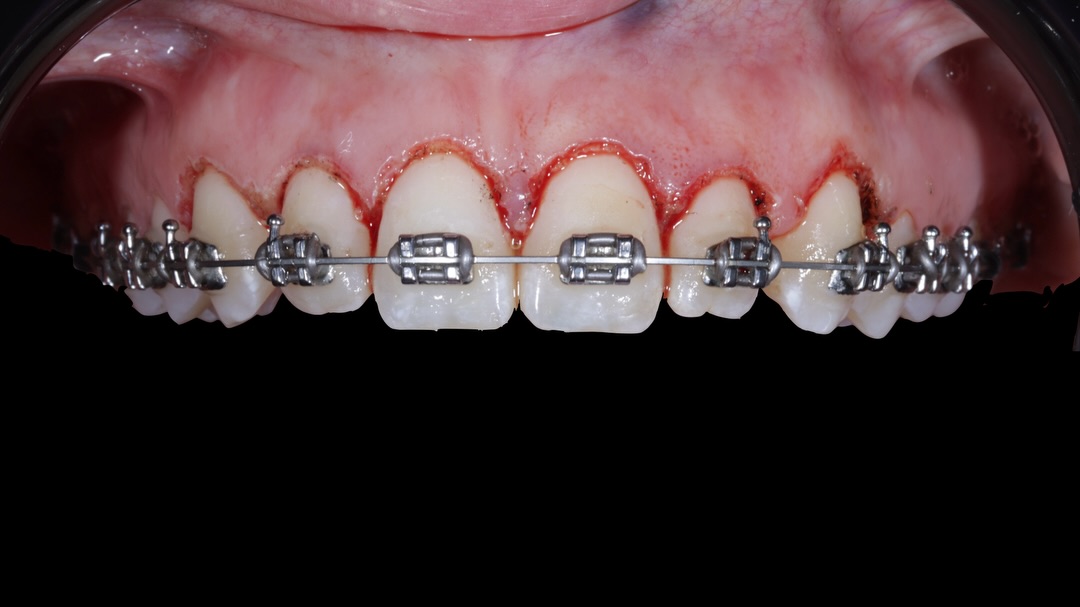

Los problemas estéticos de una sonrisa no se ciñen sólo a los dientes eso lo sabemos todos. Por eso un curso de Perio-Estética, es fundamental para poder abordar casos de Estética y solo a través de un correcto diagnóstico previo podremos realizar un adecuado plan de tratamiento, muchas

El programa aborda la técnica BOPT tanto en dientes como en implantes, presentándola como una nueva forma de entender la odontología restauradora, basada en la correcta relación entre la prótesis y los tejidos. El alumno aprenderá la filosofía BOPT aplicada a dientes, el protocolo de tallado